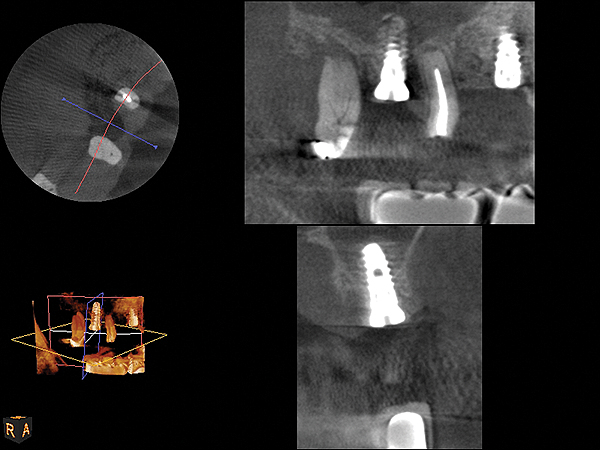

Because the bone grafting materials used in this technique need physical stability during healing to support the raised membrane, there is a high probability that significant shrinkage of the graft will occur as it heals and matures if only non-demineralized material is used. For these reasons, a composite graft using calcium sulfate, DFDBA, and mineralized particulate bone is used. A 50:50 mixture by volume of mineralized bone grafting material and DFDBA is used, to which approximately 40% calcium sulfate by volume is added. A higher percentage of calcium sulfate is used relative to that described for composite grafting in other uses, because some of the calcium sulfate will wash out during bone packing. Another advantage to this composite graft is that it is not as radiopaque as a purely mineralized graft. This allows radiographic monitoring of the bone healing around the implant, which can be used to time abutment placement on the implant. This is demonstrated in Figure 4 and Figure 5, which are radiographs taken on the day of the initial surgery showing the radiographic appearance of the composite graft, implant, and graft, and in Figure 6, a 5-month postoperative radiograph with the abutment in place. The old floor of the sinus is indistinguishable from the area of new bone. Figure 7 shows a CBCT scan (Carestream Dental, www.carestreamdental.com) taken at 4 months with the old floor of the sinus indistinguishable from the new bone formed.

Fig 4. Radiograph showing the sinus membrane being elevated about 8 mm supported by a composite bone graft that is partially radiolucent in the No. 14 position.

Figure 4

Fig 5. Radiograph of implant No. 14 and graft in place, day of placement.

Figure 5

Fig 6. 5-month postoperative radiograph showing good healing of the augmented bone with the old floor of the sinus indistinguishable.

Figure 6

Fig 7. 4-month CBCT scan (Kodak 9000D) of implant No. 14.

Figure 7

Fig 19. CBCT scan (Kodak 9000D) of implant No. 14 showing homogeneous appearance of the bone.

Figure 19

Fig 22. CBCT scan (Kodak 9000D) of No. 3 area, day of placement. Appearance of native bone and bone graft is clearly discernible.

Figure 22